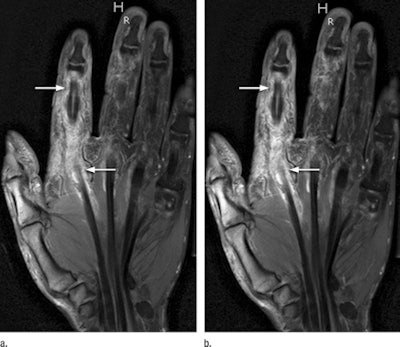

Gadobenate dimeglumine (MultiHance, Bracco) was measured in inflamed synovial tissue at half dose (0.05 mmol/kg of body weight) and at full dose (0.1 mmol/kg) using T1-weighted MRI sequences with fat saturation. Each contrast injection was followed by a 20-mL saline flush.

Two readers who were blinded to the patient data separately analyzed all images, with the half-dose and full-dose MR images mixed before evaluation. Their analysis included quantitative measurements of signal intensity in the inflamed synovial tissue, signal-to-noise ratio, and contrast-to-noise ratio.

The calculations revealed a high degree of correlation for signal intensity of synovial enhancement at the half dose and full dose of contrast. The mean signal intensity of synovial enhancement was 914.35 (± 251.1) with a half dose of contrast, compared with 1,022.6 (± 244.5) for a full dose of contrast. In the saline syringe, the average signal intensity was 642.82 (± 196.2) at half dose and 554.12 (± 162.5) at full dose.

The researchers did find, however, that the full dose of gadobenate dimeglumine had significantly better signal-to-noise and contrast-to-noise ratios than the half dose. The mean signal-to-noise ratio was 42.91 for the half dose, compared with 54.22 for the full dose, while the mean contrast-to-noise ratio was 12.81 for the half dose, compared with 24.78 for the full dose.

Despite the disparity in contrast-to-noise and signal-to-noise ratios between the dosages, the diagnostic quality of the images was not affected, according to the authors. No region of synovial inflammation seen on full-dose contrast-enhanced MRI was missed at half dose.